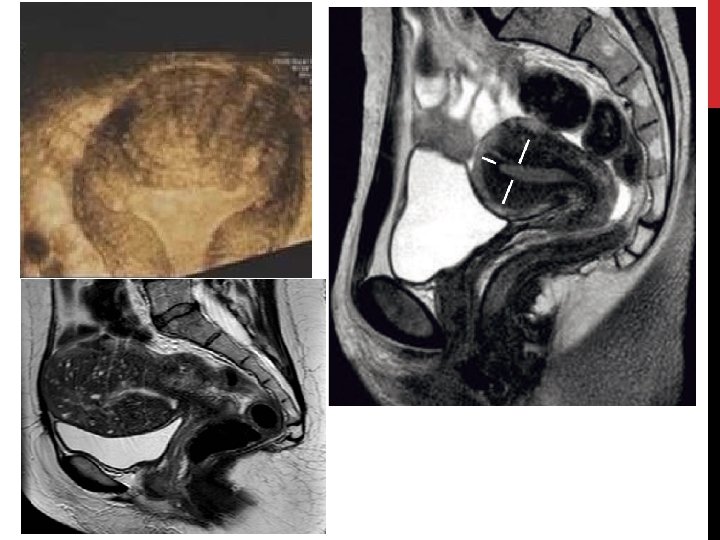

ECHOGRAPHIE PELVIENNE PAR VOIE ENDOVAGINALE: Examen de 1ère intention: • Signes directs: • Kyste endométriosique. • Nodules sous péritonéaux antérieurs et postérieurs. • Adénomyose: éléments anéchogènes au sein du myomètre. • Image hypo échogène, discrètement hétérogène. • Signes indirects: • Pseudo kyste péritonéal: trouble de résorption du liquide péritonéal (adhérences). • Hydro/hématosalpinx: obturation tubaire complète. • « kissings ovaries » : infiltration rétractante et adhérentielle des nodules des LUS. + échographie rénale à la recherche d’une hydronéphrose, surtout si présence d’un nodule de l’espace antérieur.

IRM PELVIENNE • Permet une cartographie des lésions d’endométriose profonde. • Intérêt dans le bilan pré opératoire: • Compartiment ant • Compartiment post • Non recommandée à titre systématique • Oui si suspicion d’endométriose profonde • Non pour le diagnostic des endométriomes en dehors de situations particulières

BILAN COMPARTIMENT MOYEN • Concerne l’utérus, les annexes, les ligaments ronds, larges et le vagin. • Ovaires: 20 -40%. • Informations majeures: • Présence d’endométriome. • Perméabilité tubaire. • EEV: seul examen nécessaire dans la majorité des atteintes. • Se 89%, Spé 91%, VPP 84%, VPN 94, 5%. • Évaluation de la réserve ovarienne (CFA) • Recherche dilatation tubaire. • IRM: • Pour éliminer une EPP associée ou pour diagnostic différentiel kyste ovarien. • Se 90%, Spé 98%, précision 96%. • CR: nombre, taille endométriomes, recherche dilatation urétérale, rapport avec les organes voisins, recherche de salpinx, éliminer EPP. • HSG: • Évaluation de la distension et perméabilité tubaire • Limites: invasif, risque de FN (spasme tubaire), risques infectieux. • gold standard: cœlioscopie + test de perméabilité tubaire.

BILAN COMPARTIMENT POSTÉRIEUR • Recherche: • Adénomyose externe • Lésion intestinale: nombre, taille, infiltration et sténose, distance // marge anale • Envahissement vaginal postérieur • EEV: • Atteinte LUS, vaginale et cloison recto vaginale: Se 81%/50%/11%, Spé 75%/96%/100%. • IRM: • Atteinte LUS, vaginale et recto vaginale: Se 76%/80%, Spé 83%/95%/98%. • Bonne corrélation avec le siège de la lésion et l’évaluation // marge anale. • Mais ne précise pas l’extension dans la paroi intestinale (séreuse et/ou musculeuse) et Se moyenne pour atteinte vagin et cloison RV. • opacification rectale et vaginale par gel pour diminuer ces limites. • EER: distance // marge anale, en cas de doute ou discordance (moins performante pour atteinte sous muqueuse rectale). • Colo scanner: • Identification lésions intestinales: Se 98, 7%, Spé 100%, VPP 100%, VPN 95, 7%. • Meilleure Se que EEV dans le dépistage des lésions rectales + degré d’infiltration. • Autres: • Coloscopie: NON • Colo. TDM à l’air: complète les données de l’IRM, l’EEV et l’EER. • Entéro IRM: pour lésions au dessus de la jonction recto sigmoïdienne.

ADÉNOMYOSE (2) • Diagnostic clinique: • • • Examen normal dans 65% des cas. TV: utérus augmenté de volume, dur, fibreux, à contours réguliers, +- sensible pendant les règles. Diagnostic radiologique: • Echographie endovaginale: Se 82, 5%, Spé 84, 6% • • • IRM pelvienne: Se 77, 5%, Spé 92%, VPN 88, 5%, VPP 92% • • Utérus volumineux non expliqué par la présence de fibromes. Asymétrie des parois myométriales antérieure ou postérieure. Aspect strié du myomètre. Zone hétérogène myométriale, lacunes hypo échogènes myométriales, nodules hyperéchogènes. Épaississement ZJ en T 2 > 12 mm. Présences de zones focales hypo intenses. Spots hyper. T 2 myométriaux. Echographie 3 D: • • • Anomalie de la ZJ avec zones hyperéchogènes. Perte de l’aspect triangulaire de la cavité en coupe coronale. Vascularisation en peigne.